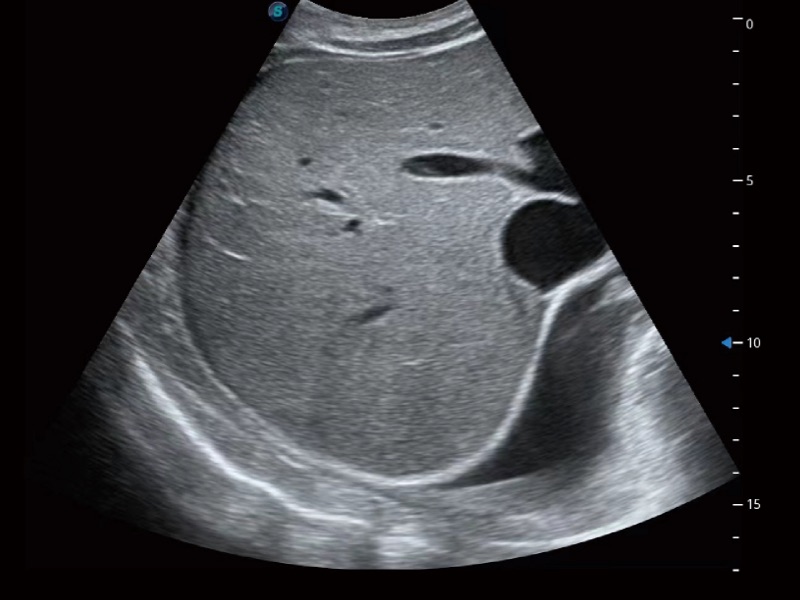

腹部应用

微米成像技术大大提高了器官和病变的可见性。高清对比度分辨率将抑制斑点噪声,同时保持真实的组织结构。

宽频带及多频段变频结合乐玩lewin国际频率复合技术,使得每一支探头可以很好地给临床带来穿透力与分辨率的完美结合,图像真实,提供临床诊断准确性。